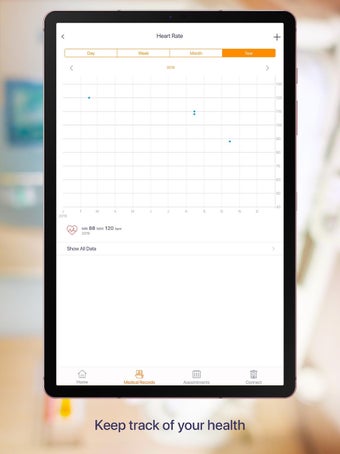

Carepassport là một ứng dụng Android cung cấp cho bệnh nhân một giải pháp toàn diện để quản lý dữ liệu y tế của họ. Ứng dụng cho phép bệnh nhân truy cập và lưu trữ an toàn dữ liệu y tế của mình, lên lịch hẹn, xem hình ảnh y tế, báo cáo xét nghiệm và lâm sàng từ các nhà cung cấp khác nhau, và chia sẻ chúng bằng công nghệ tính toán di động tiên tiến. Với Carepassport, bệnh nhân có thể dễ dàng quản lý nhu cầu chăm sóc sức khỏe của mình chỉ với vài lần chạm trên thiết bị di động của họ.

Một trong những tính năng quan trọng nhất của ứng dụng là việc truy cập dữ liệu y tế một chạm dễ dàng. Bệnh nhân có thể truy cập dữ liệu y tế của mình hoặc dữ liệu đại diện gia đình một cách an toàn và nhanh chóng, làm cho nó trở thành một công cụ tuyệt vời để quản lý lịch sử bệnh án của họ. Ứng dụng cũng cho phép người dùng tìm kiếm các phòng khám và bệnh viện gần đó, lên lịch hẹn, và thậm chí nhận chỉ đường đến cuộc hẹn của họ qua Uber. Ngoài ra, bệnh nhân có thể giao tiếp với nhà cung cấp chăm sóc của họ qua tin nhắn an toàn, chia sẻ hình ảnh y tế và cho phép thành viên gia đình truy cập dữ liệu y tế của họ thông qua cài đặt proxy an toàn. Cuối cùng, ứng dụng cung cấp tài liệu giáo dục liên quan đến chăm sóc sức khỏe và có thể kết nối với các thiết bị đeo được hoặc nhập dữ liệu y tế thủ công.